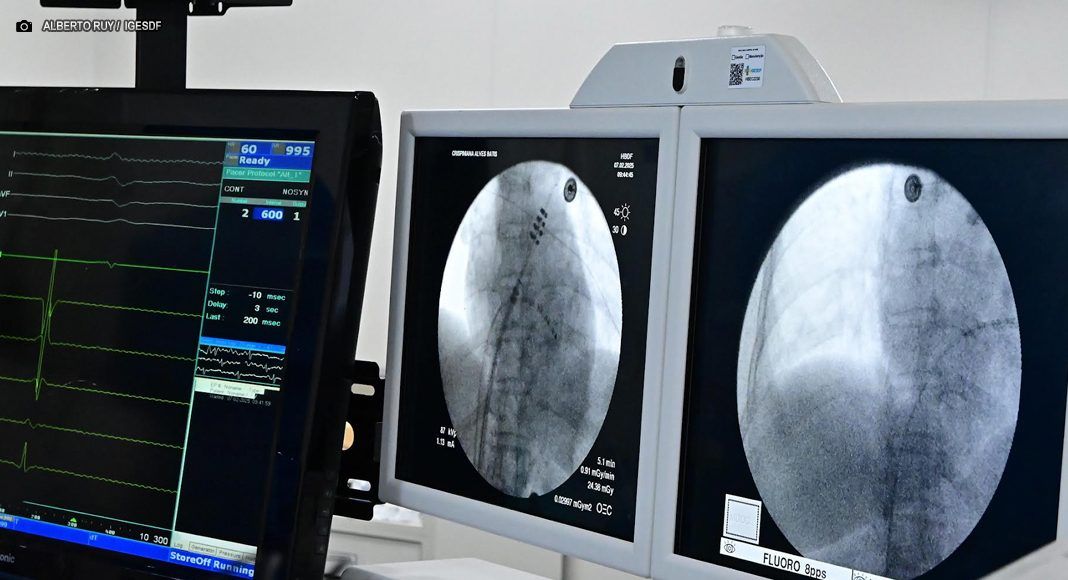

Novo procedimento é minimamente invasiva não exige centro cirúrgico, UTI, anestesia geral nem internação prolongad – Foto: Alberto Ruy/ IgesDF

Os primeiros dois pacientes submetidos à nova técnica no Hospital de Base foram um homem e uma mulher, ambos hipertensos, sendo que um deles já havia sofrido um infarto anteriormente. A eletrofisiologista relata que os procedimentos foram concluídos com sucesso absoluto, sem intercorrências. “O tempo de sala foi significativamente reduzido em comparação com as tecnologias anteriores, o que é um ganho importante tanto para os pacientes quanto para o hospital”, enfatiza.

Uma das principais vantagens da nova técnica é a possibilidade de realizá-la fora do ambiente cirúrgico tradicional, no próprio setor de hemodinâmica, garantindo mais agilidade e segurança para os pacientes.